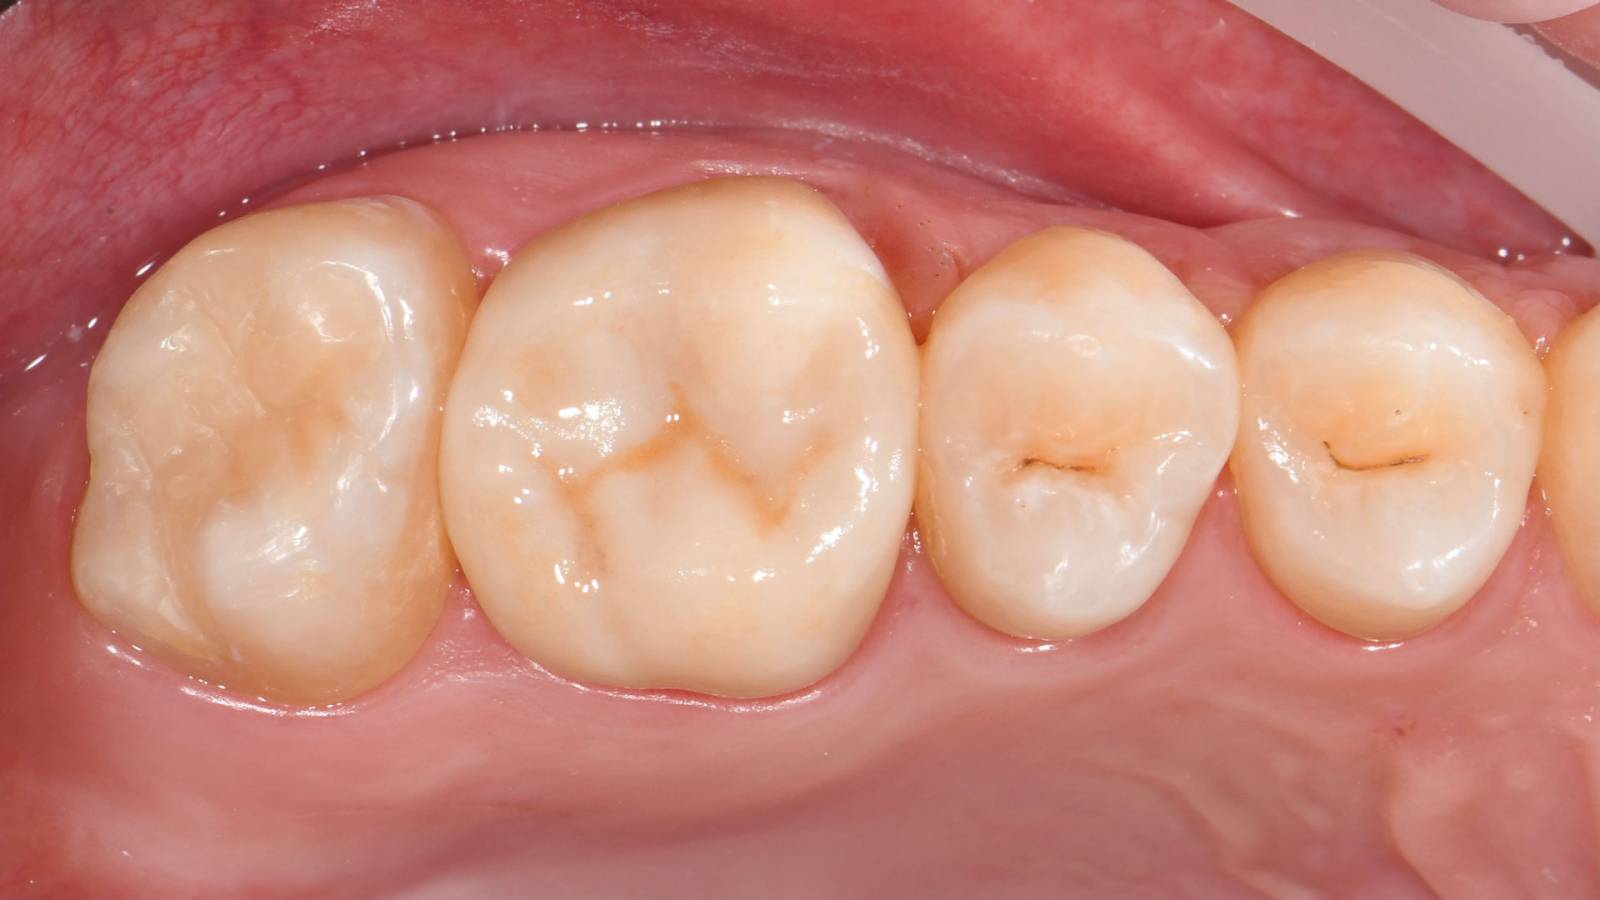

Before: Insufficient fillings in the second quadrant. The restorations were about 15 years old.

After: Chairside-fabricated crowns made from CEREC Tessera (teeth 26/27). Inlays for teeth 24 and 25 made of composite blocks.

Quadrant rehabilitation

Two CEREC Tessera crowns and two inlays

Within a single visit of four hours the restoration of two crowns and two inlays, which were 15 years old, was carried out. The patient was very pleased with the very good esthetic result.